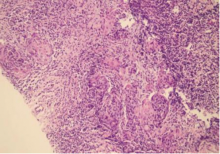

晚期及复发性宫颈癌治疗方式有限,预后差,免疫治疗为近期备受关注的一种宫颈癌治疗手段。现报道1例综合阳性评分为100分的宫颈癌复发患者免疫治疗疗效,该患者单靶点免疫药物治疗10个月余出现疾病进展,考虑免疫耐药,通过分析该患者的临床资料,并复习相关文献,以提高对宫颈癌免疫治疗及耐药机制的认识。